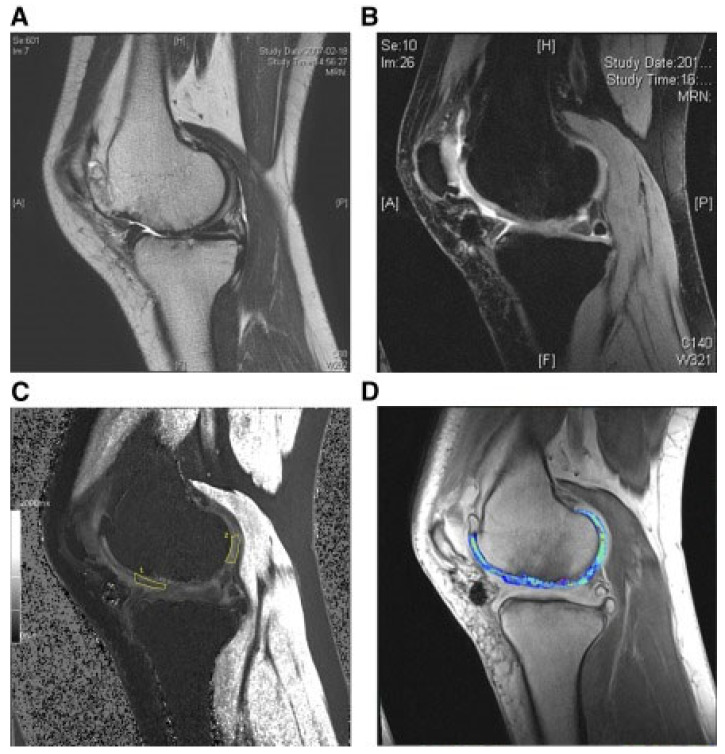

還評估了人臍帶血來源的間充質(zhì)干細(xì)胞(HUCB-MSC)治療軟骨再生的安全性和有效性。根據(jù)國際軟骨修復(fù)協(xié)會的數(shù)據(jù),HUCB-MSC用于治療7名患有KLIII級OA和IV級軟骨缺損的患者。同種異體HUCB-MSC在體外生長,然后與HA水凝膠結(jié)合并應(yīng)用于損傷部位。微骨折方案與這些細(xì)胞結(jié)合使用。12周后,修復(fù)的組織似乎成熟,24周后,臨床評分增加。在整個7年隨訪過程中,臨床改善的穩(wěn)定性也值得注意。組織學(xué)用于在手術(shù)后一年顯示透明軟骨,而MRI用于在手術(shù)后3年顯示軟骨再生,如圖所示圖3(其中釓-DTPA用作造影劑,以藍(lán)色顯示)。

(A) 術(shù)前軟骨缺損。(B) 移植后3年軟骨再生。(C) 通過在標(biāo)記區(qū)域采樣來計算相對軟骨松弛率的變化。(D) 顯示與藍(lán)色信號相關(guān)的GAG含量增加。